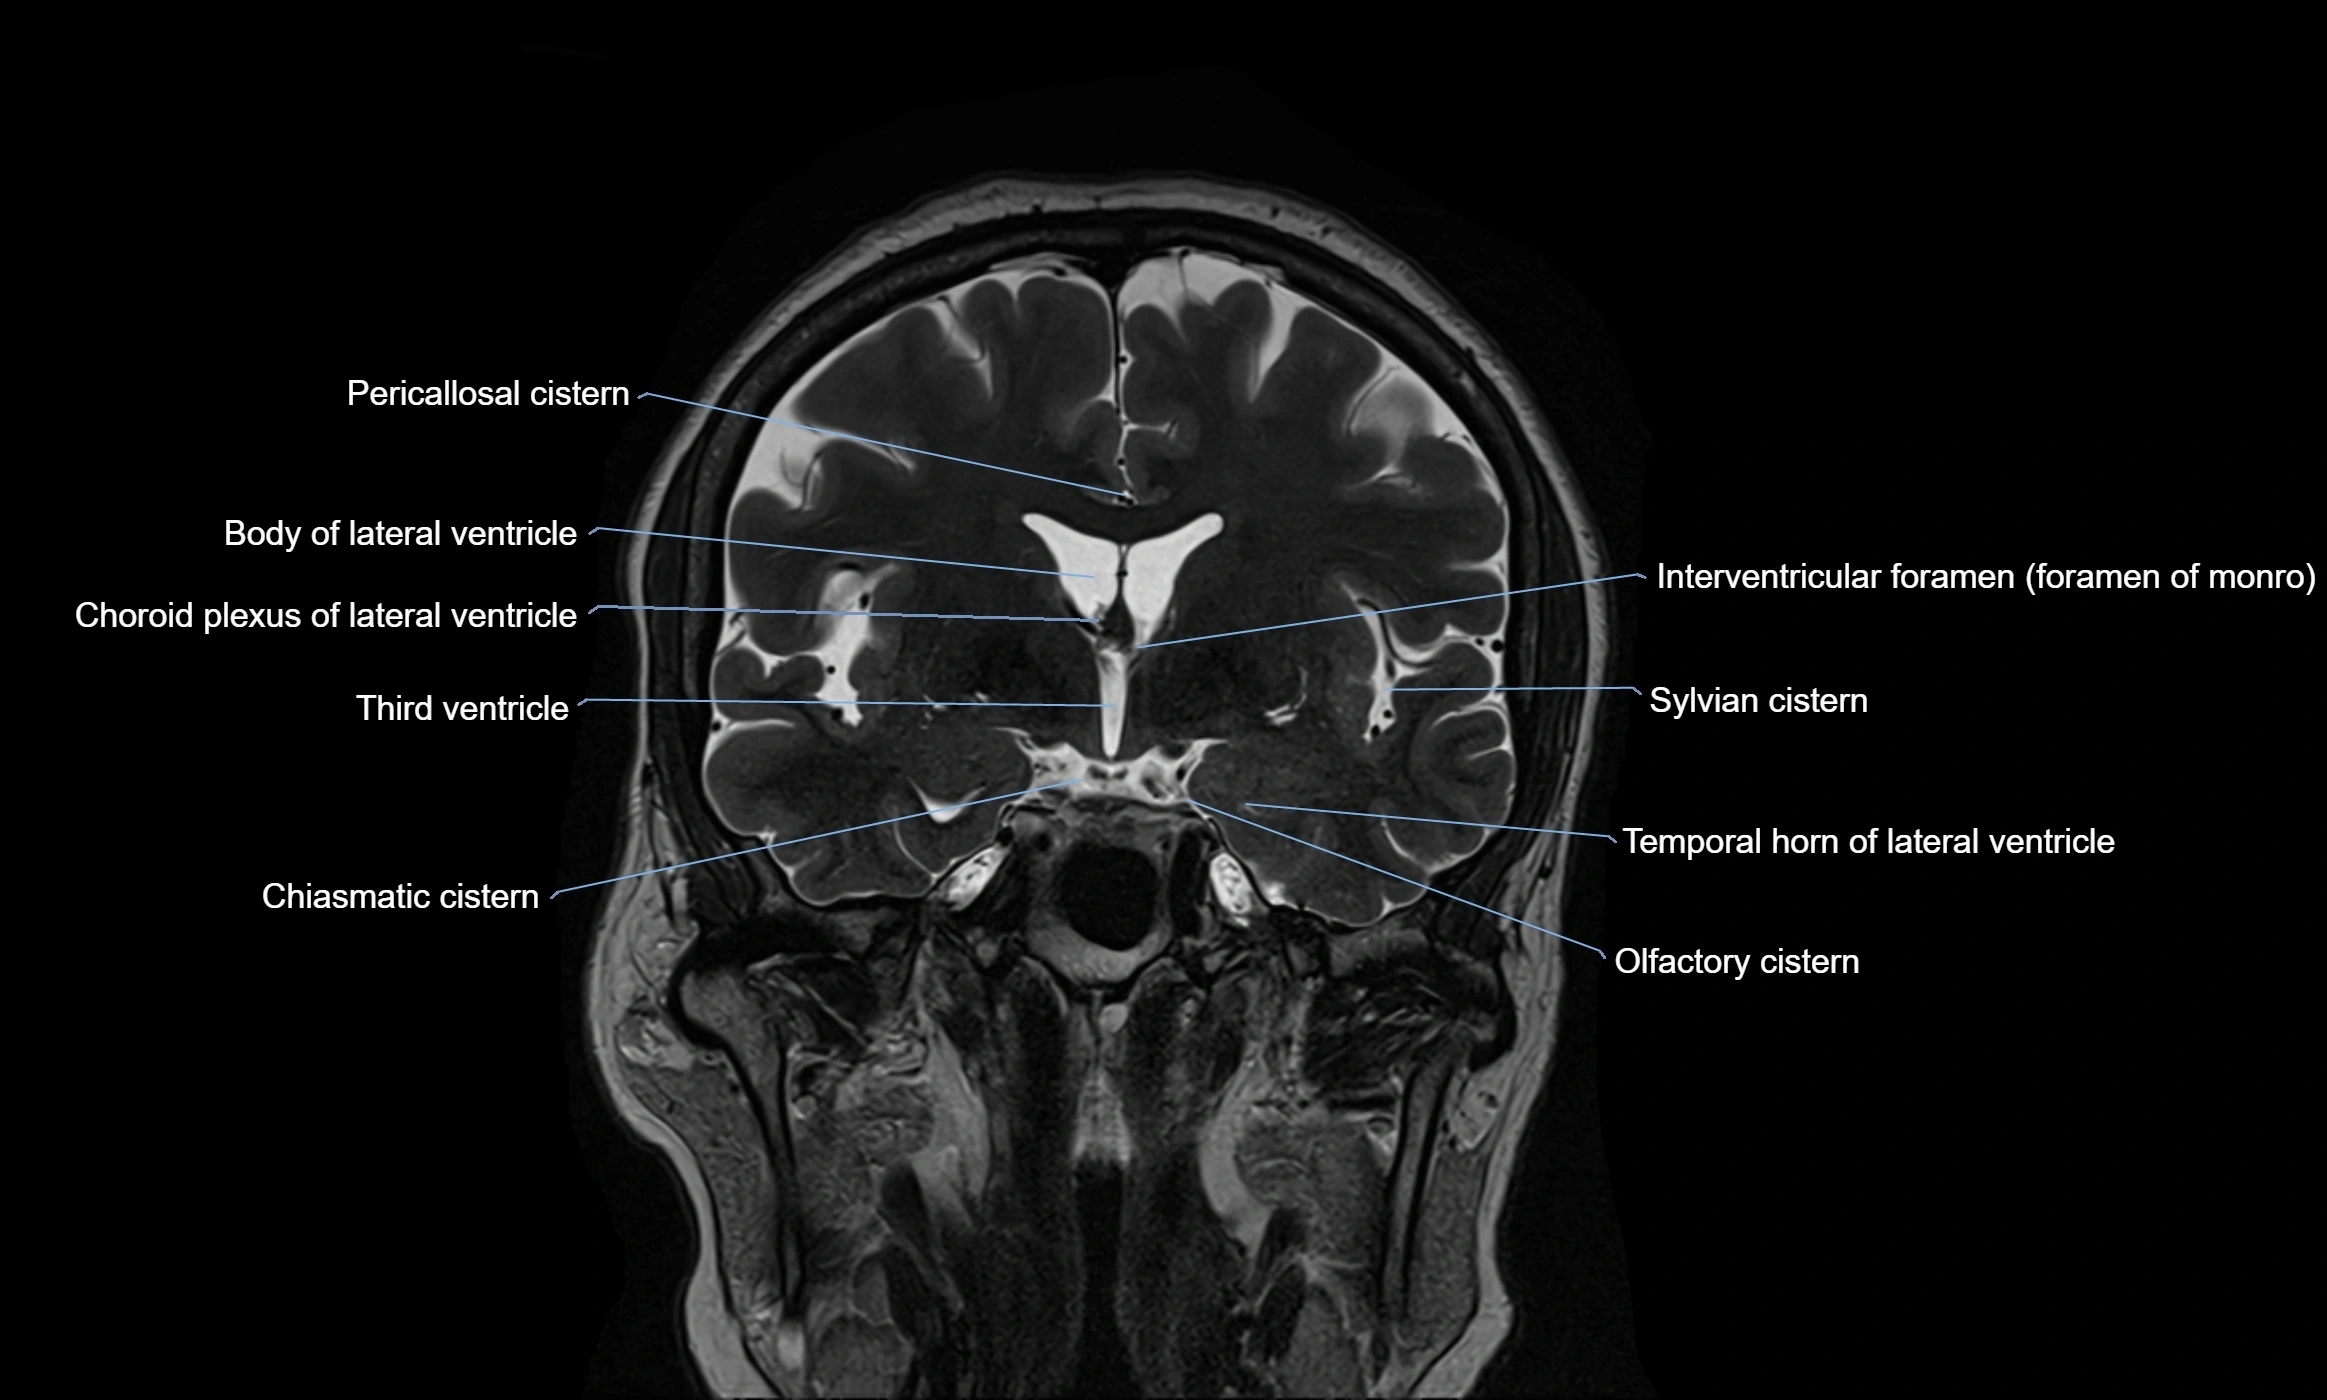

MRI images

image